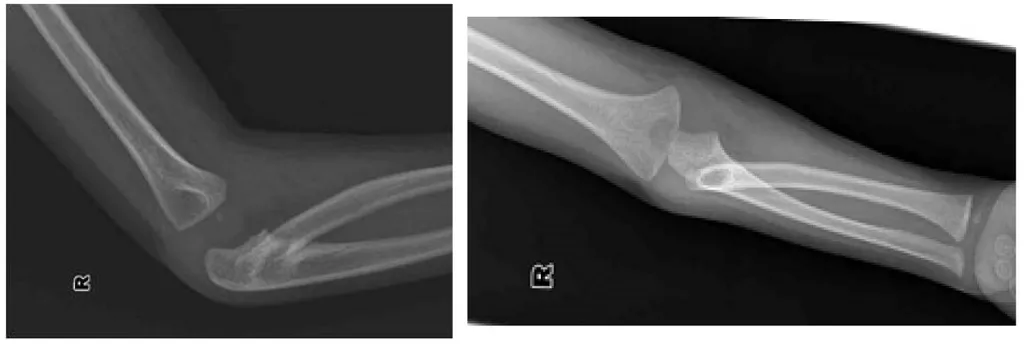

這張X光片顯示的是兒童常見的「牽拉肘」(nursemaid's elbow),也就是橈骨頭半脫位,這種情況最主要影響前臂的旋轉動作,尤其是旋後。圖片中橈骨頭與肱骨小頭的正常對位關係明顯異常,是判斷的關鍵。